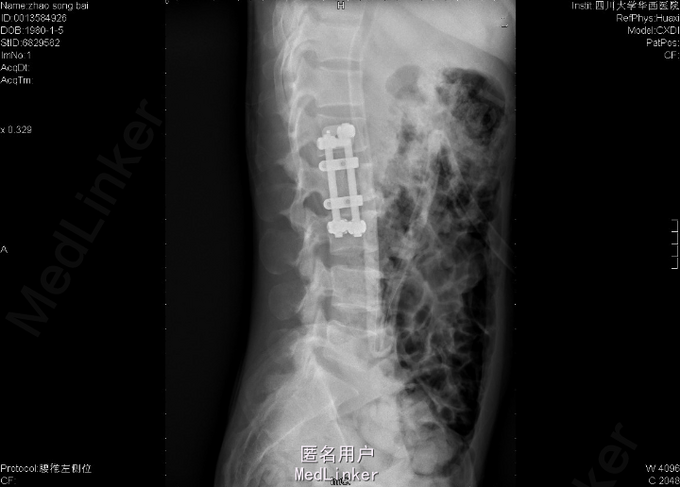

胸骨结核术后1年半,腰背疼痛活动受限1年。 入院前1年半,患者胸部正中无明显诱因出现一包块,无红肿、发烫、乏力、消瘦、潮热、盗汗、腹痛、下肢及会阴麻木等症状,在当地行手术治疗,术中发现侵犯胸骨,术后病检为:“胸骨结核”,术后予以利福平 0.45 qd及异烟肼 0.3 qd抗痨治疗,术后伤口经久不愈,后改利福平为利福喷汀 0.45 biw抗痨,院外一直换药及口服抗痨药治疗。入院前1年,患者无明显诱因出现腰背疼痛,伴弯腰困难,仍无乏力、消瘦、潮热、盗汗、腹痛、下肢及会阴麻木等症状,在当地行腰椎CT示:“腰2椎体结核”,继续予以原抗痨方案治疗,腰痛无明显缓解。入院前1+月,患者到我院就诊,门诊建议抗痨方案更改为:利福喷汀 0.45 biw、异烟肼 0.3 qd、乙胺丁醇 0.75 qd继续抗痨,建议抗痨后住院手术治疗。

查体:生命体征平稳,体温正常,心肺腹无异常,脊柱腰段轻度后凸畸形,胸部正中可见一长约3cm手术瘢痕,可见一大小约0.5cm×0.5cm痂壳未脱落,少许渗液,腰部压痛、叩痛存在,左侧腹股沟触痛觉减退,会阴部感觉未见明显异常,双下肢肌张力正常,双下肢肌力正常,双侧膝反射、踝反射正常引出,巴氏征(-)。患者复查血常规、肝肾功正常,血沉:83mm/h,CRP:42.3mg/l。

诊断:1,腰1、2、3椎结核;2、胸骨结核术后伤口经久不愈;3、低蛋白血症;4、右侧股总静脉反流;5、双肺结核;6、右侧胸膜增厚;7、脾脏增大;8、左肾囊肿。 处理:抗痨,加强营养支持,卧床休息,手术。